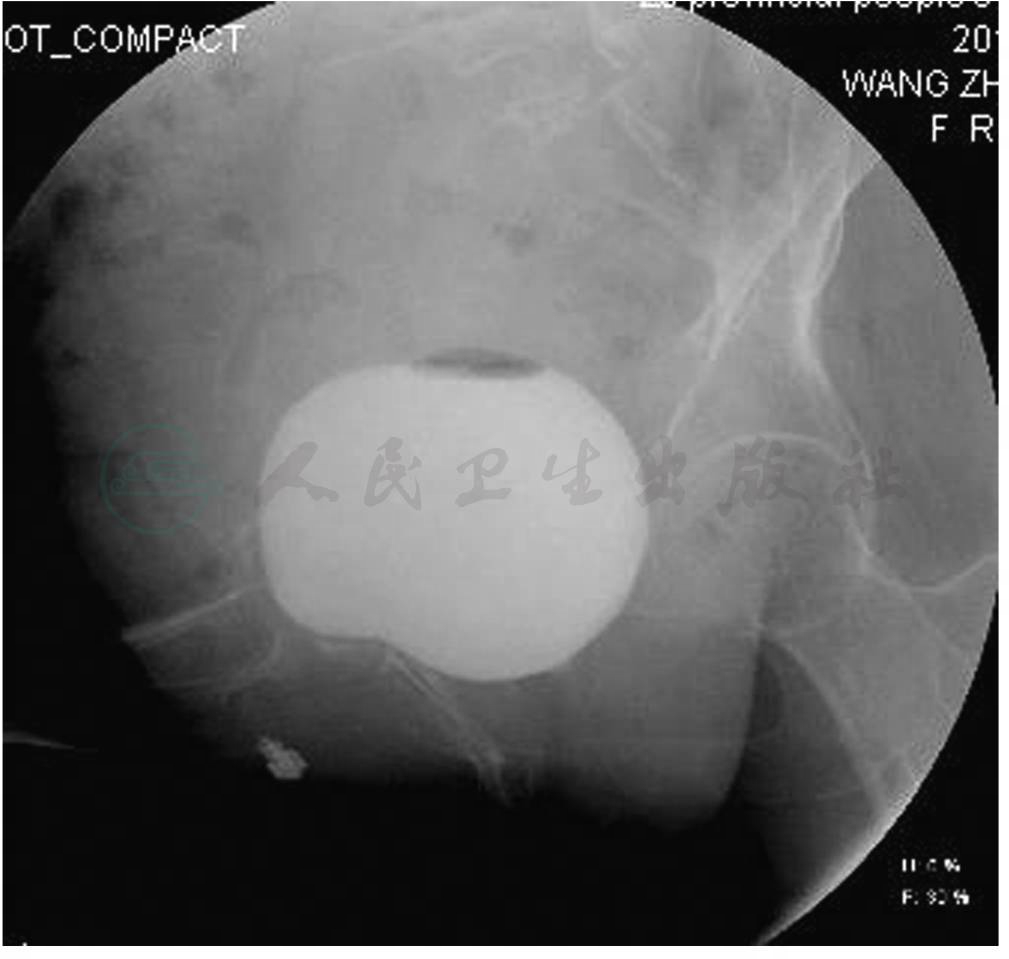

患者女,67岁,因“反复尿频、尿急、尿痛1年”入院。相关辅助检查:①泌尿系增强CT诊断(图1):膀胱左后壁局部增厚,乙状结肠局部管壁增厚,考虑乙状结肠肿瘤侵及膀胱左后壁可能大。②膀胱造影未见明显异常(图2)。③膀胱镜检查示膀胱左侧壁可疑瘘口。其他常规检查及查体未见明显异常。

图2 膀胱造影